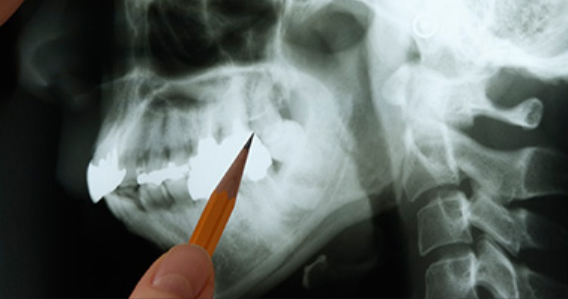

매복된 사랑니는 3D 첨단 CT촬영으로 상태를 정밀검사하고 발치계획을 세웁니다.

다양한 상태의 사랑니들을 다루어본 경험이 풍부하기 때문에 잇몸 속에

매복되어 보이지 않는 사랑니 발치가 가능합니다.

사랑니 발치 시에는 뿌리가 신경관과 근접해 있는지 또 어느쪽으로 휘어져 있는지를

파악해야 훨씬 더 안전하고 편하게

또 빠르게 뽑을 수 있습니다.

최첨단 3차원 CT를 이용하여 사랑니 뿌리의 위치와

신경관 위치 등을 정밀하게 분석한 후 시행하고 있습니다.